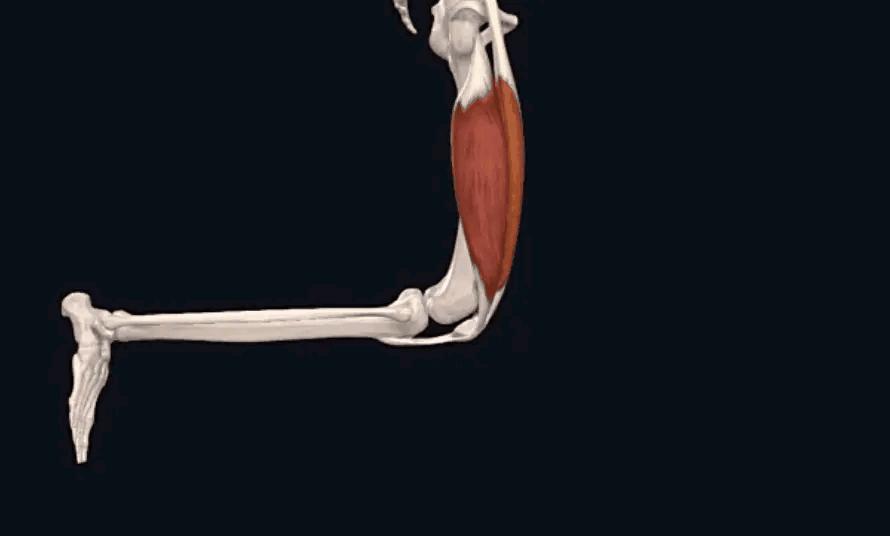

主要是长在骨头上的肌肉和韧带。在膝盖的四周都有不同的肌肉、韧带,从不同的角度发力来维持膝关节和膝盖骨的稳定;倘若哪一侧太弱,其他侧太强,就会打破原有的稳定状态,出现不同的腿型、不同方向的膝盖骨移位。

正常情况下 ,如动图所示,在您屈膝(弯腿)的时候,膝盖骨(俗称菠萝盖)会往内下方移动;而伸膝(伸腿)的时候,膝盖骨会往外上方移动。

倘若您的腿型不正常(往往没有人给您分析评估,易被认为是正常的),如您存在X型腿或O型腿,每天都要行走、跑跳、下蹲,必然要弯腿和伸腿,不知不觉发生膝盖骨的异常活动,即运动的 轨迹不正常 ,将会导致膝盖骨和大腿骨之间产生不正常的应力刺激,引发疼痛。